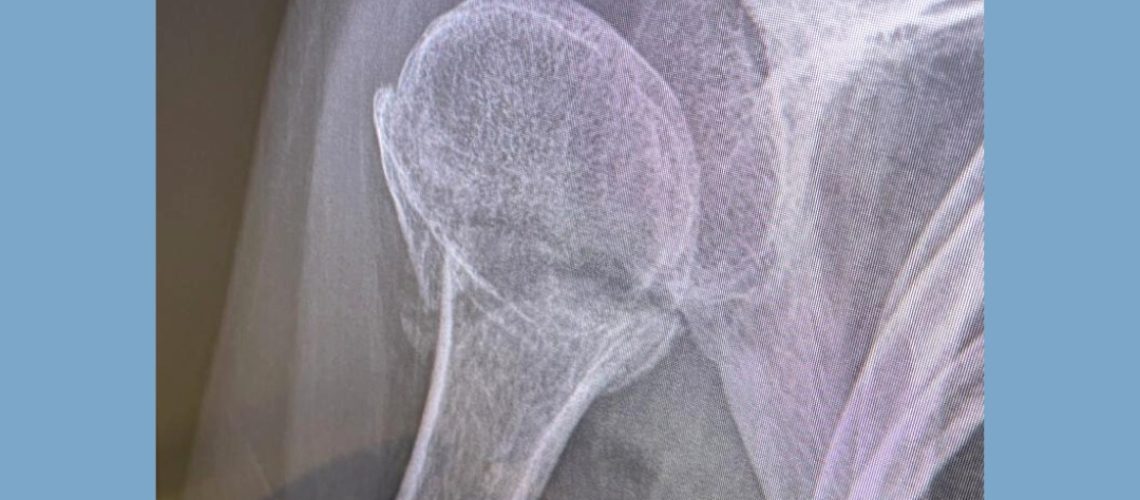

Hace unos días llegó Gonzalo con esta lesión, tras 4 semanas con inmovilización con cabestrillo para comenzar su rehabilitación. En las siguientes imágenes podéis visualizar la ecografía que le realizamos en la clínica, como el tac y la radiografía que trajo el paciente. 🦴🩻🖥️